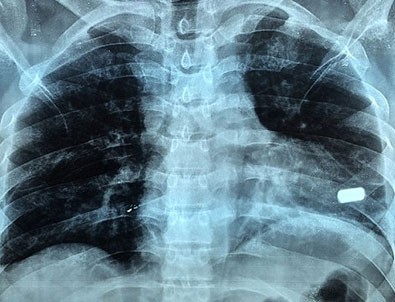

Sonunda 5 kişilik kardiyoloji ekibi Sharma'nın kalbine müdahale etti. 23 Eylül'de gerçekleşen operasyonda kalbin sol kapakçığına 1 milim saplanan kurşun çıkarıldı.Sharma sağlığına kavuşurken doktorlar kalbine kurşun saplanmasına rağmen hayatta kalan adamı yaşayan mucize olarak tanımladı.